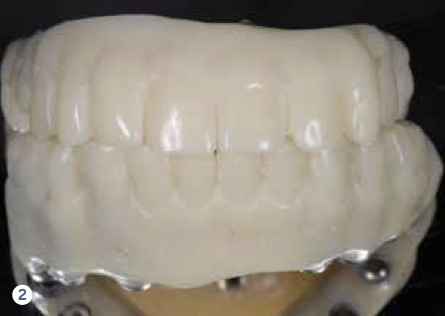

Fig 2. Utilizing temporary abutments and cold-cure acrylic resin, a spare set is ready and available in case repair is needed, providing optimal contingency measurements.

Figure 2

Considering contingency during treatment planning forces clinicians to create a solution for a problem they know will or can occur. It focuses on providing solutions to problems after the implant treatment develops the anticipated complications. For example, a spare set of the implant-supported reconstruction was fabricated utilizing temporary abutments and cold-cure acrylic resin for use if and when a repair of the definitive prosthesis was needed (Figure 1 and Figure 2).